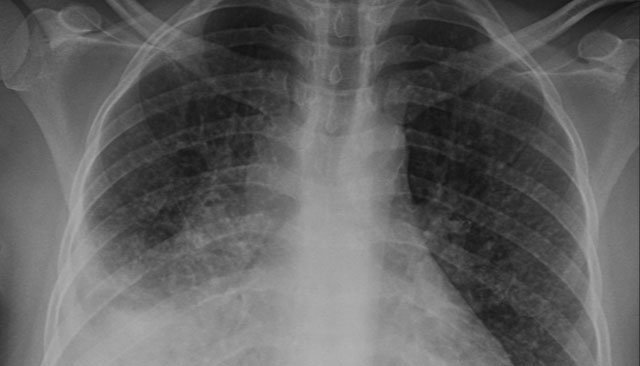

Le poumon est le lieu privilégié de la tuberculeuse, représentant ainsi près de la moitié des cas enregistrés, soit 47% des tuberculoses pulmonaires contre 53% des localisations extra-pulmonaires, a précisé le ministère à l'occasion de la journée mondiale de la tuberculose.

Cela a permis de réaménager les centres de diagnostic de la tuberculose et des maladies respiratoires, de les équiper en appareils numériques de radiologie et en technologie de pointe basée sur la biologie moléculaire, tout en assurant la gratuité de toutes les prestations sanitaires à tous les patients tuberculeux.